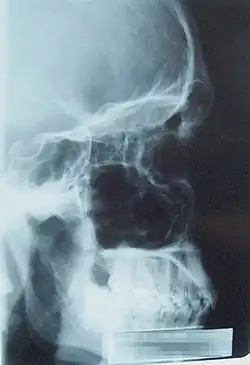

Lateral view paranasal sinus |

Pneumosinus dilatans is a rare, generally benign, asymptomatic disease of unknown etiology that is characterized by the enlargement of one or more paranasal sinuses without any sign of bone loss or pathological alterations to the mucosa beneath.[1]

Clinical examination is used to make the diagnosis, and radiography (plain film or CT) is used to confirm it when the characteristic sinus enlargement is observed.[3]